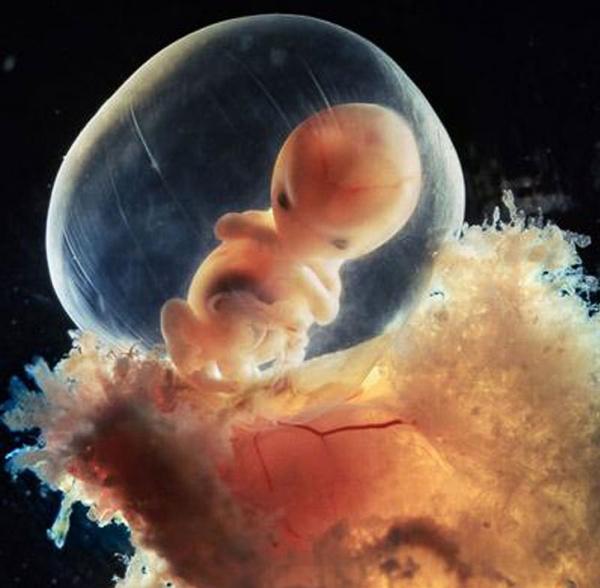

8 εβδομάδων

10 εβδομάδων. Τα βλέφαρα είναι ήδη λίγο ανοιγμένα. Σε μερικές ημέρες θα είναι τελείως σχηματισμένα

Στις 10 εβδομάδες το έμβρυο ήδη χρησιμοποιεί τα χέρια του για να μελετήσει το περιβάλλον